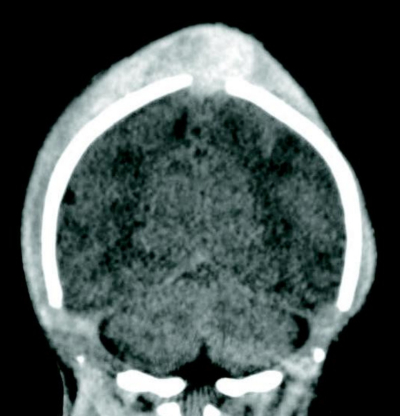

血液所見:赤血球 180 万、Hb 6.8 g/dL、Ht 18 %、白血球 28,000、血小板20 万、出血時間正常、PT-INR 1.1(基準 0.9〜1.1)、APTT 122 秒(基準 27〜40)、フィブリノゲン 262 mg/dL(基準 130〜380)。頭部 CT 冠状断像を別に示す。